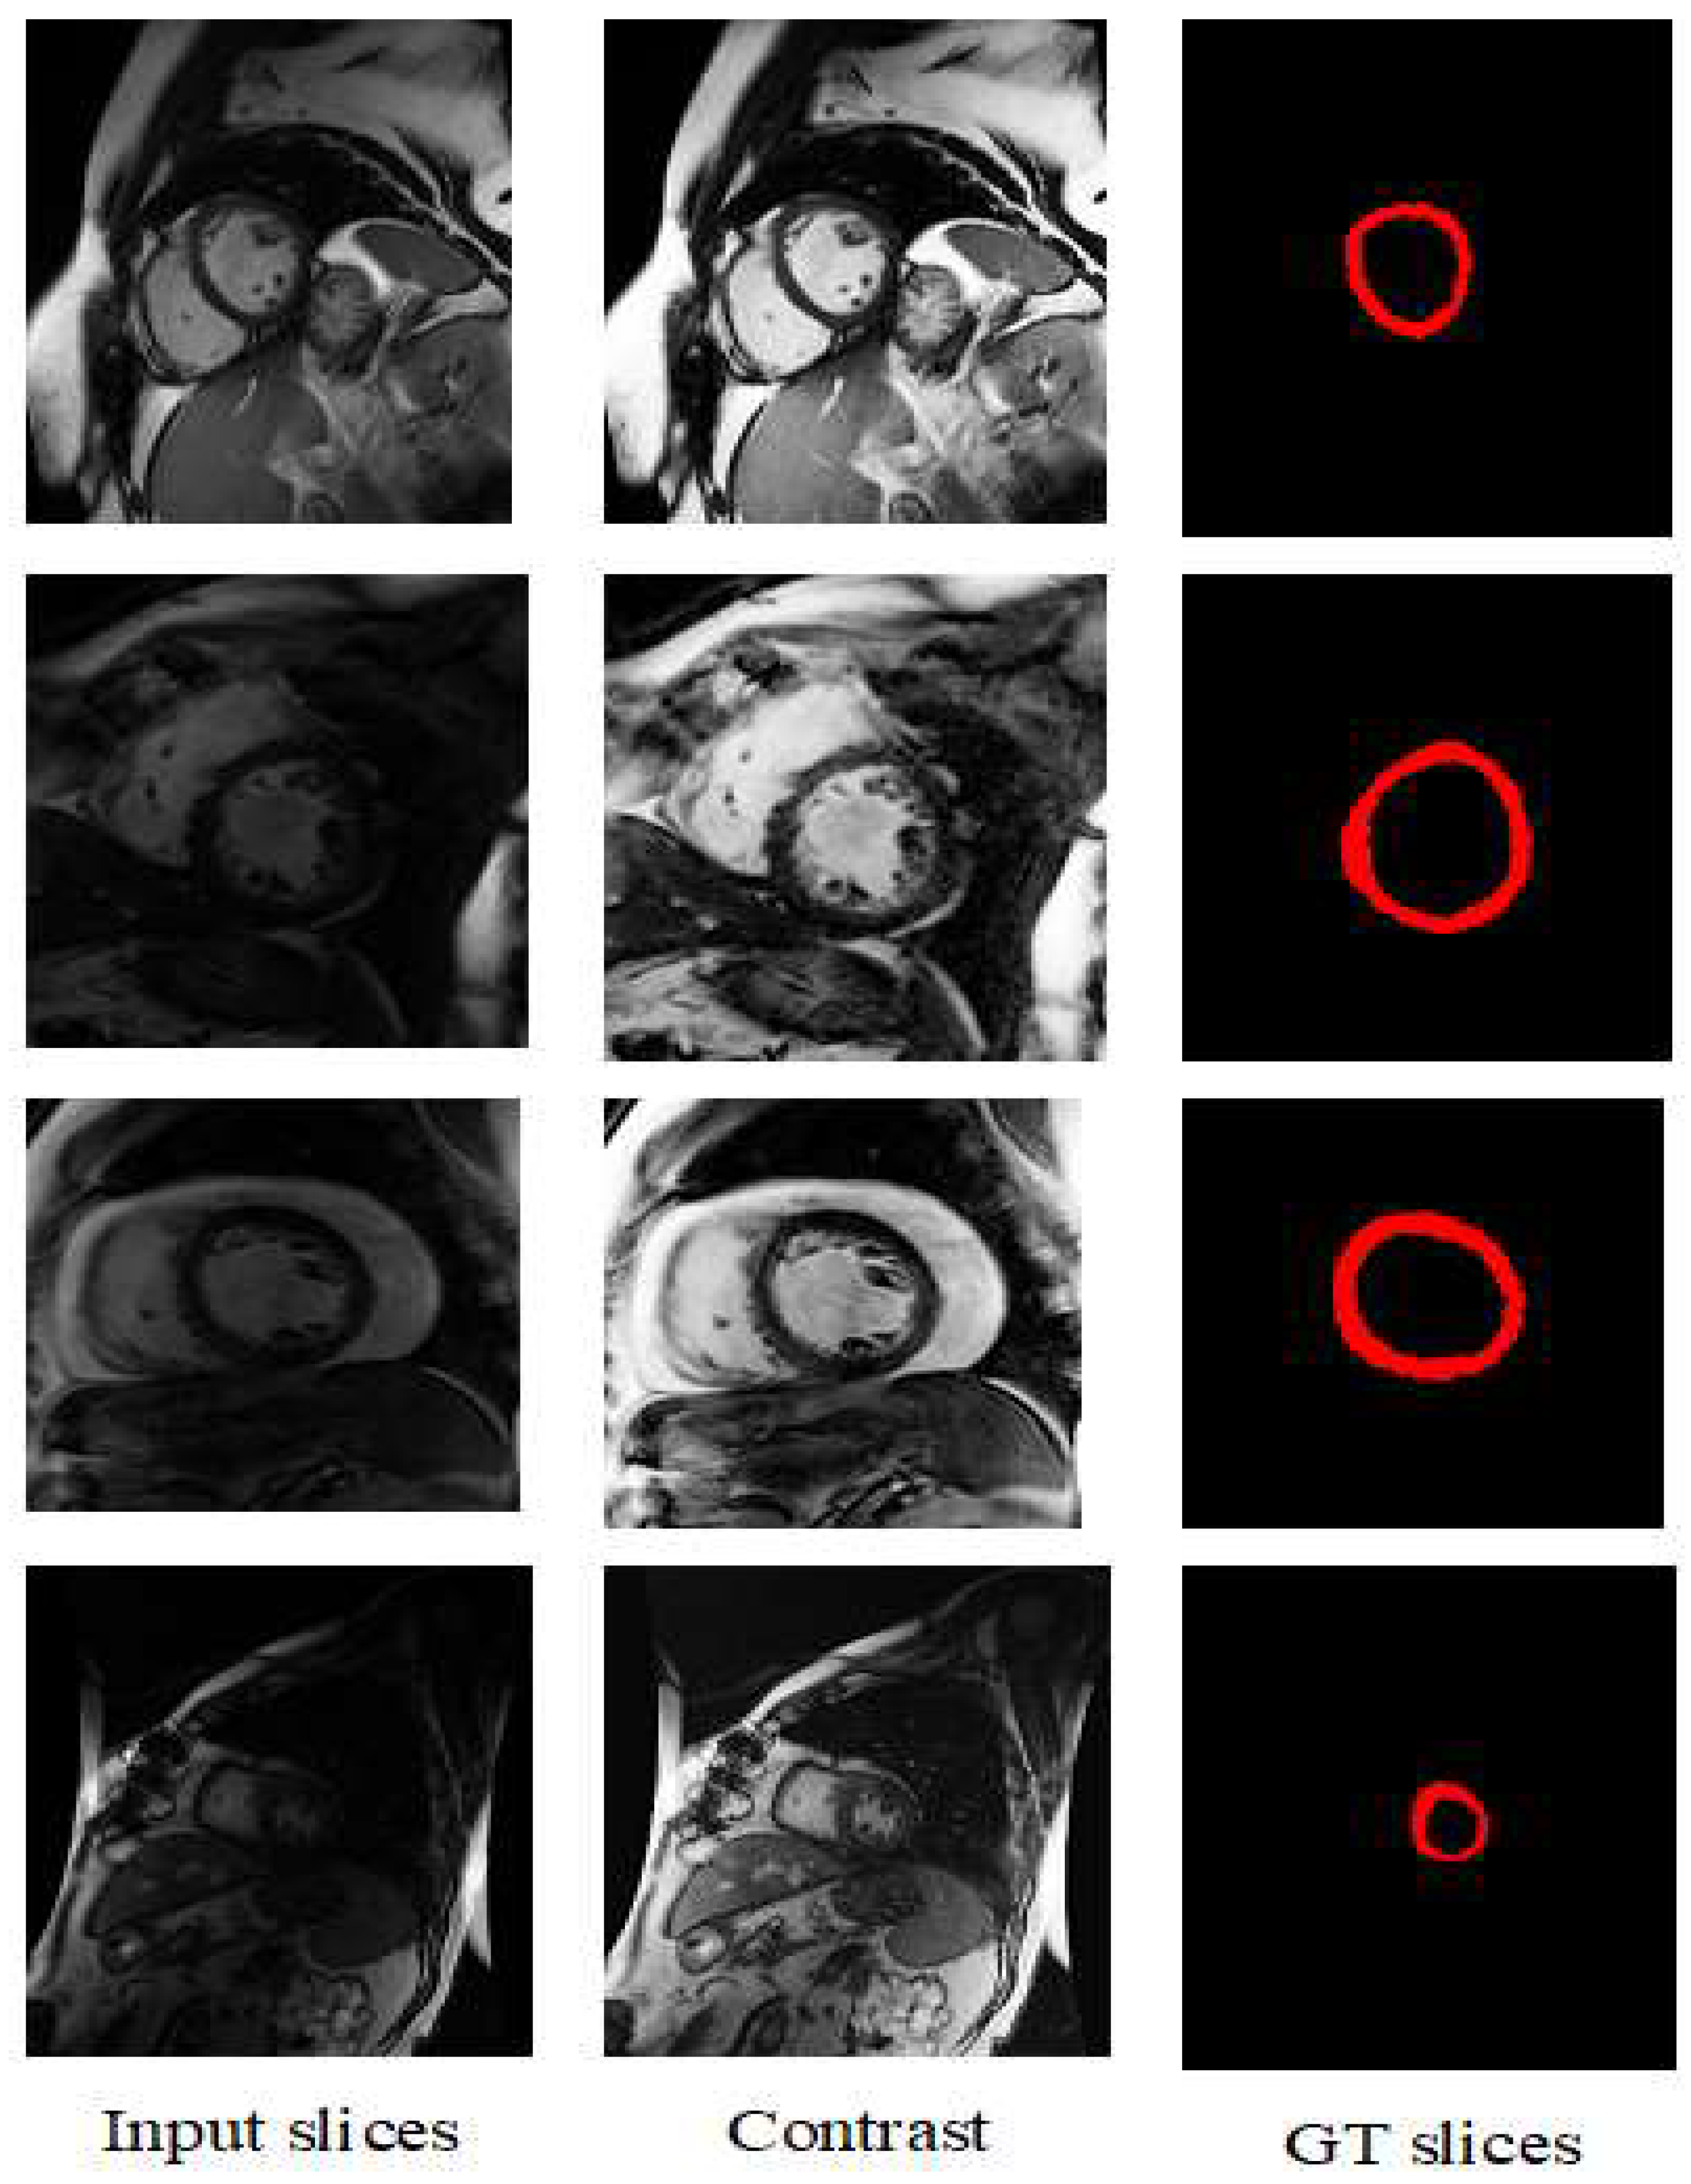

3.2. Preprocessing of the Dataset

- A contrast enhancement method is proposed for preprocessing the input cardiac MRI dataset. Various performance metrics are used to relate the performance of recent models and the proposed model in deep learning contexts.